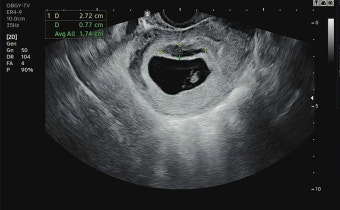

임신 5주차는 본격적으로 임신 여부를 확인하고 병원을 방문해야 하는 시기입니다. 가정용 임신 테스트기에서 양성이 나왔다면, 산부인과를 방문해 정확한 진단을 받아야 합니다. 혈액 검사와 초음파 검사를 통해 자궁 내에 정상적으로 착상되었는지 확인할 수 있습니다.

이 시기에 병원을 방문하면 태아의 위치, 착상 여부, 다태아 여부 등을 확인할 수 있고, 임신 유지에 필요한 초기 상담과 검진을 받을 수 있습니다. 특히 자궁외 임신이나 유산의 위험을 조기에 발견할 수 있기 때문에, 병원 방문은 절대 미루지 말아야 합니다.

5주차의 태아는 아직 매우 작으며 약 1.5~2mm 정도입니다. 이 시기에는 신경관이 형성되며, 뇌와 척수가 점차 구체적인 형태를 갖추게 됩니다. 심장 역시 이 시기부터 박동을 시작하며, 초음파를 통해 심박동이 관찰될 수도 있습니다. 비록 눈에 띄는 외형은 없지만, 태아의 주요 기관들이 형성되는 시기이므로 영양 섭취와 생활습관에 신경 써야 할 중요한 시기입니다.